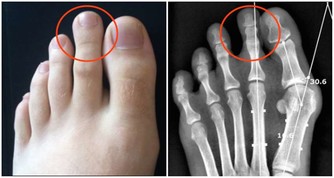

人體的腸道有8到10米長,平均每隔3.5公分就有一個彎折,即使是每天都排便,還會存在很多食物殘渣的堆積,它們在細菌的作用下乾結、腐敗、發酵,日積月累,這些食物殘渣最終形成厚達5-7毫米,重達5-6公斤的黑色、惡臭、有毒的物質,這些就是俗稱的宿便。